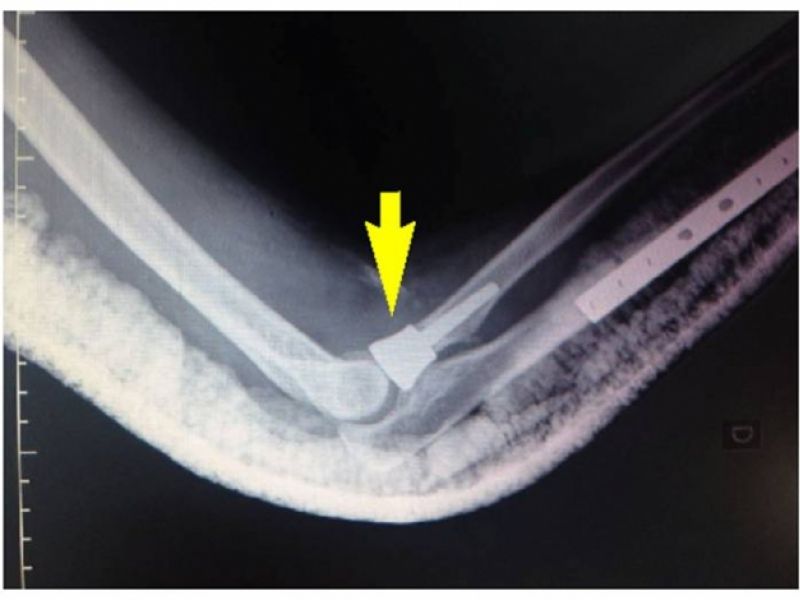

Cirurgia evita incapacitação de pacientes em tarefas que exijam esforço